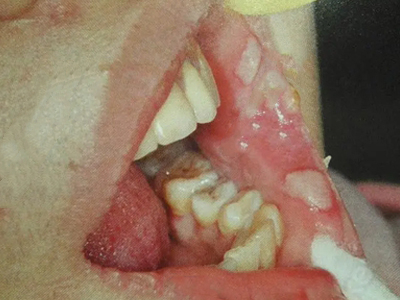

二期口腔梅毒会出现梅毒性黏膜炎及梅毒黏膜斑症状,梅毒性黏膜炎好发于舌、唇黏膜及口角等处,表现为黏膜充血、弥漫性潮红,可有糜烂。舌背有大小不一的光滑区,舌乳头消失。

梅毒黏膜斑是二期梅毒最常见的口腔损害。可发生在口腔黏膜的任何部位,以唇黏膜最多见,其次为软腭、舌背、舌底等部位。损害呈灰白色、光亮而微隆的斑块,圆形或椭圆形,直径约1cm,边界清楚。易发生糜烂或浅表溃疡,表面覆盖灰白色假膜,周围有红晕。黏膜斑常为多个,内含有大量梅毒螺旋体。